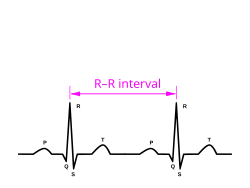

A more precise method of determining heart rate involves the use of an electrocardiograph, or ECG (also abbreviated EKG). An ECG generates a pattern based on electrical activity of the heart, which closely follows heart function. Continuous ECG monitoring is routinely done in many clinical settings, especially in critical care medicine. On the ECG, instantaneous heart rate is calculated using the R wave-to-R wave (RR) interval and multiplying/dividing in order to derive heart rate in heartbeats/min. Multiple methods exist:

- HR = 1000 · 60/(RR interval in milliseconds)

- HR = 60/(RR interval in seconds)

- HR = 300/number of "large" squares between successive R waves.

- HR= 1,500 number of large blocks

Standard textbooks of physiology and medicine mention that heart rate (HR) is readily calculated from the ECG as follows: HR = 1000*60/RR interval in milliseconds, HR = 60/RR interval in seconds, or HR = 300/number of large squares between successive R waves. In each case, the authors are actually referring to instantaneous HR, which is the number of times the heart would beat if successive RR intervals were constant.